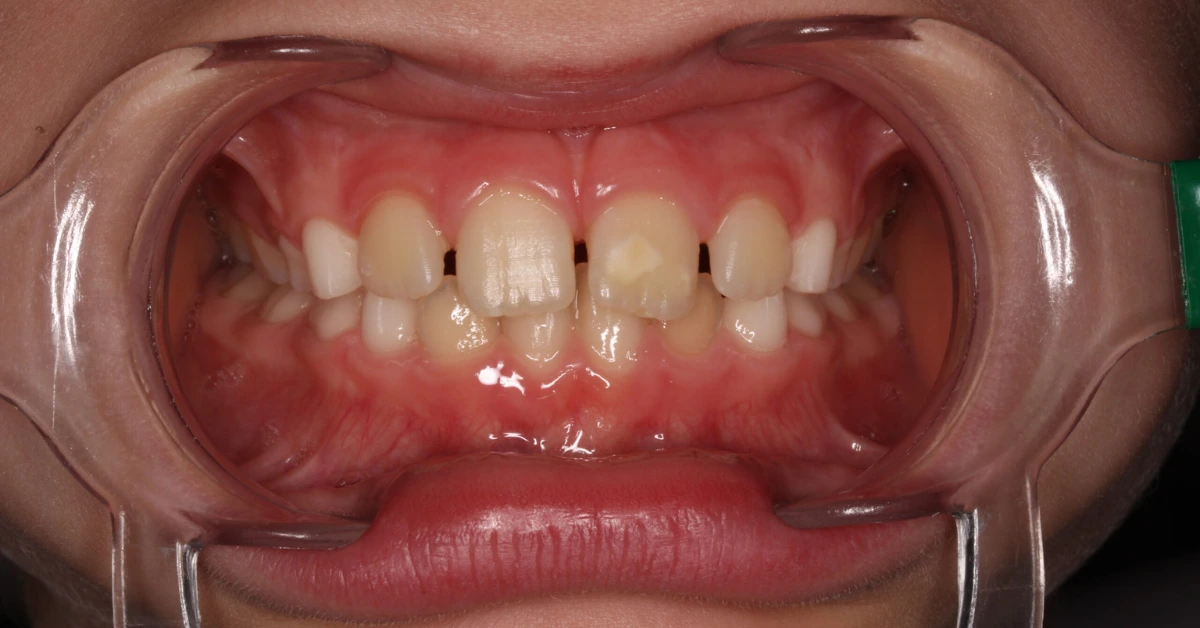

Manchas brancas/castanhas nos incisivos e molares?

A hipomineralização incisivo-molar é uma alteração da estrutura do esmalte bastante frequente. A forma de os pais relatarem esta condição é dizerem “os dentes do meu filho, quando nasceram, já vinham assim”.

A sua origem resulta durante a amelogénese, numa disfunção dos ameloblastos em maturar o esmalte. Clinicamente verificam-se manchas (opacidades) na superfície dentária, que podem ter coloração branca leitosa, creme, amarela ou acastanhada, principalmente na região dos 2/3 mais incisais ou dos 2/3 mais oclusais. Quanto mais escuros forem os defeitos, mais fraco é o esmalte.

O principal problema desta condição é, nos molares, a elevada sensibilidade (pela porosidade) e susceptibilidade à fratura, e nos incisivos, é a estética.